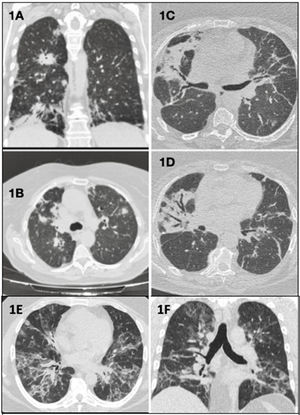

Caso clínico 1: mujer de 70 años, con febrícula e infiltrados pulmonares bilaterales en la tomografía computarizada de tórax (TC) (fig. 1A y B) refractarios al tratamiento antibiótico y corticoideo. La biopsia pulmonar quirúrgica (BPQ) mostró un linfoma B difuso de célula grande primario pulmonar (LBDCG-PP), actualmente en remisión tras quimioterapia (QT) R-CHOP (rituximab, ciclofosfamida, doxorrubicina, vincristina y prednisona).

Plano coronal (A) y plano axial (B): consolidaciones parenquimatosas bilaterales con distribución peribroncovascular, periférica y subpleural. Planos axiales (C y D): opacidades atelectásicas-fibróticas bilaterales de distribución peribroncovascular, con bronquiectasias y bronquielectasias de tracción. Plano axial (E) y plano coronal (F): opacidades alvéolo-intersticiales con distribución bilateral y peribroncovasculares que coexisten con otras de localización periféricas en vidrio deslustrado y de aspecto en bandas.

Caso clínico 2: mujer de 63 años con infiltrados alveolares bilaterales (fig. 1C y D), con expresión en sangre periférica del 2,3% linfocitos B clonales kappa. La BPQ mostró infiltración por linfocitos B, confirmándose en la biopsia de médula ósea invasión por un linfoma B de zona marginal de tejido linfoide asociado a mucosas pulmonar (LPP-MALT). Se procedió a una resección pulmonar con adyuvancia con rituximab.

Caso clínico 3: hombre de 37 años con tos, rash cutáneo y opacidades alveolares en la TC (fig. 1E y F). La BPQ mostró infiltrado de linfocitos B atípicos infectados por virus de Epstein-Barr (VEB), estableciéndose el diagnóstico de granulomatosis linfomatoide (GL) grado 1, decidiéndose actitud expectante.